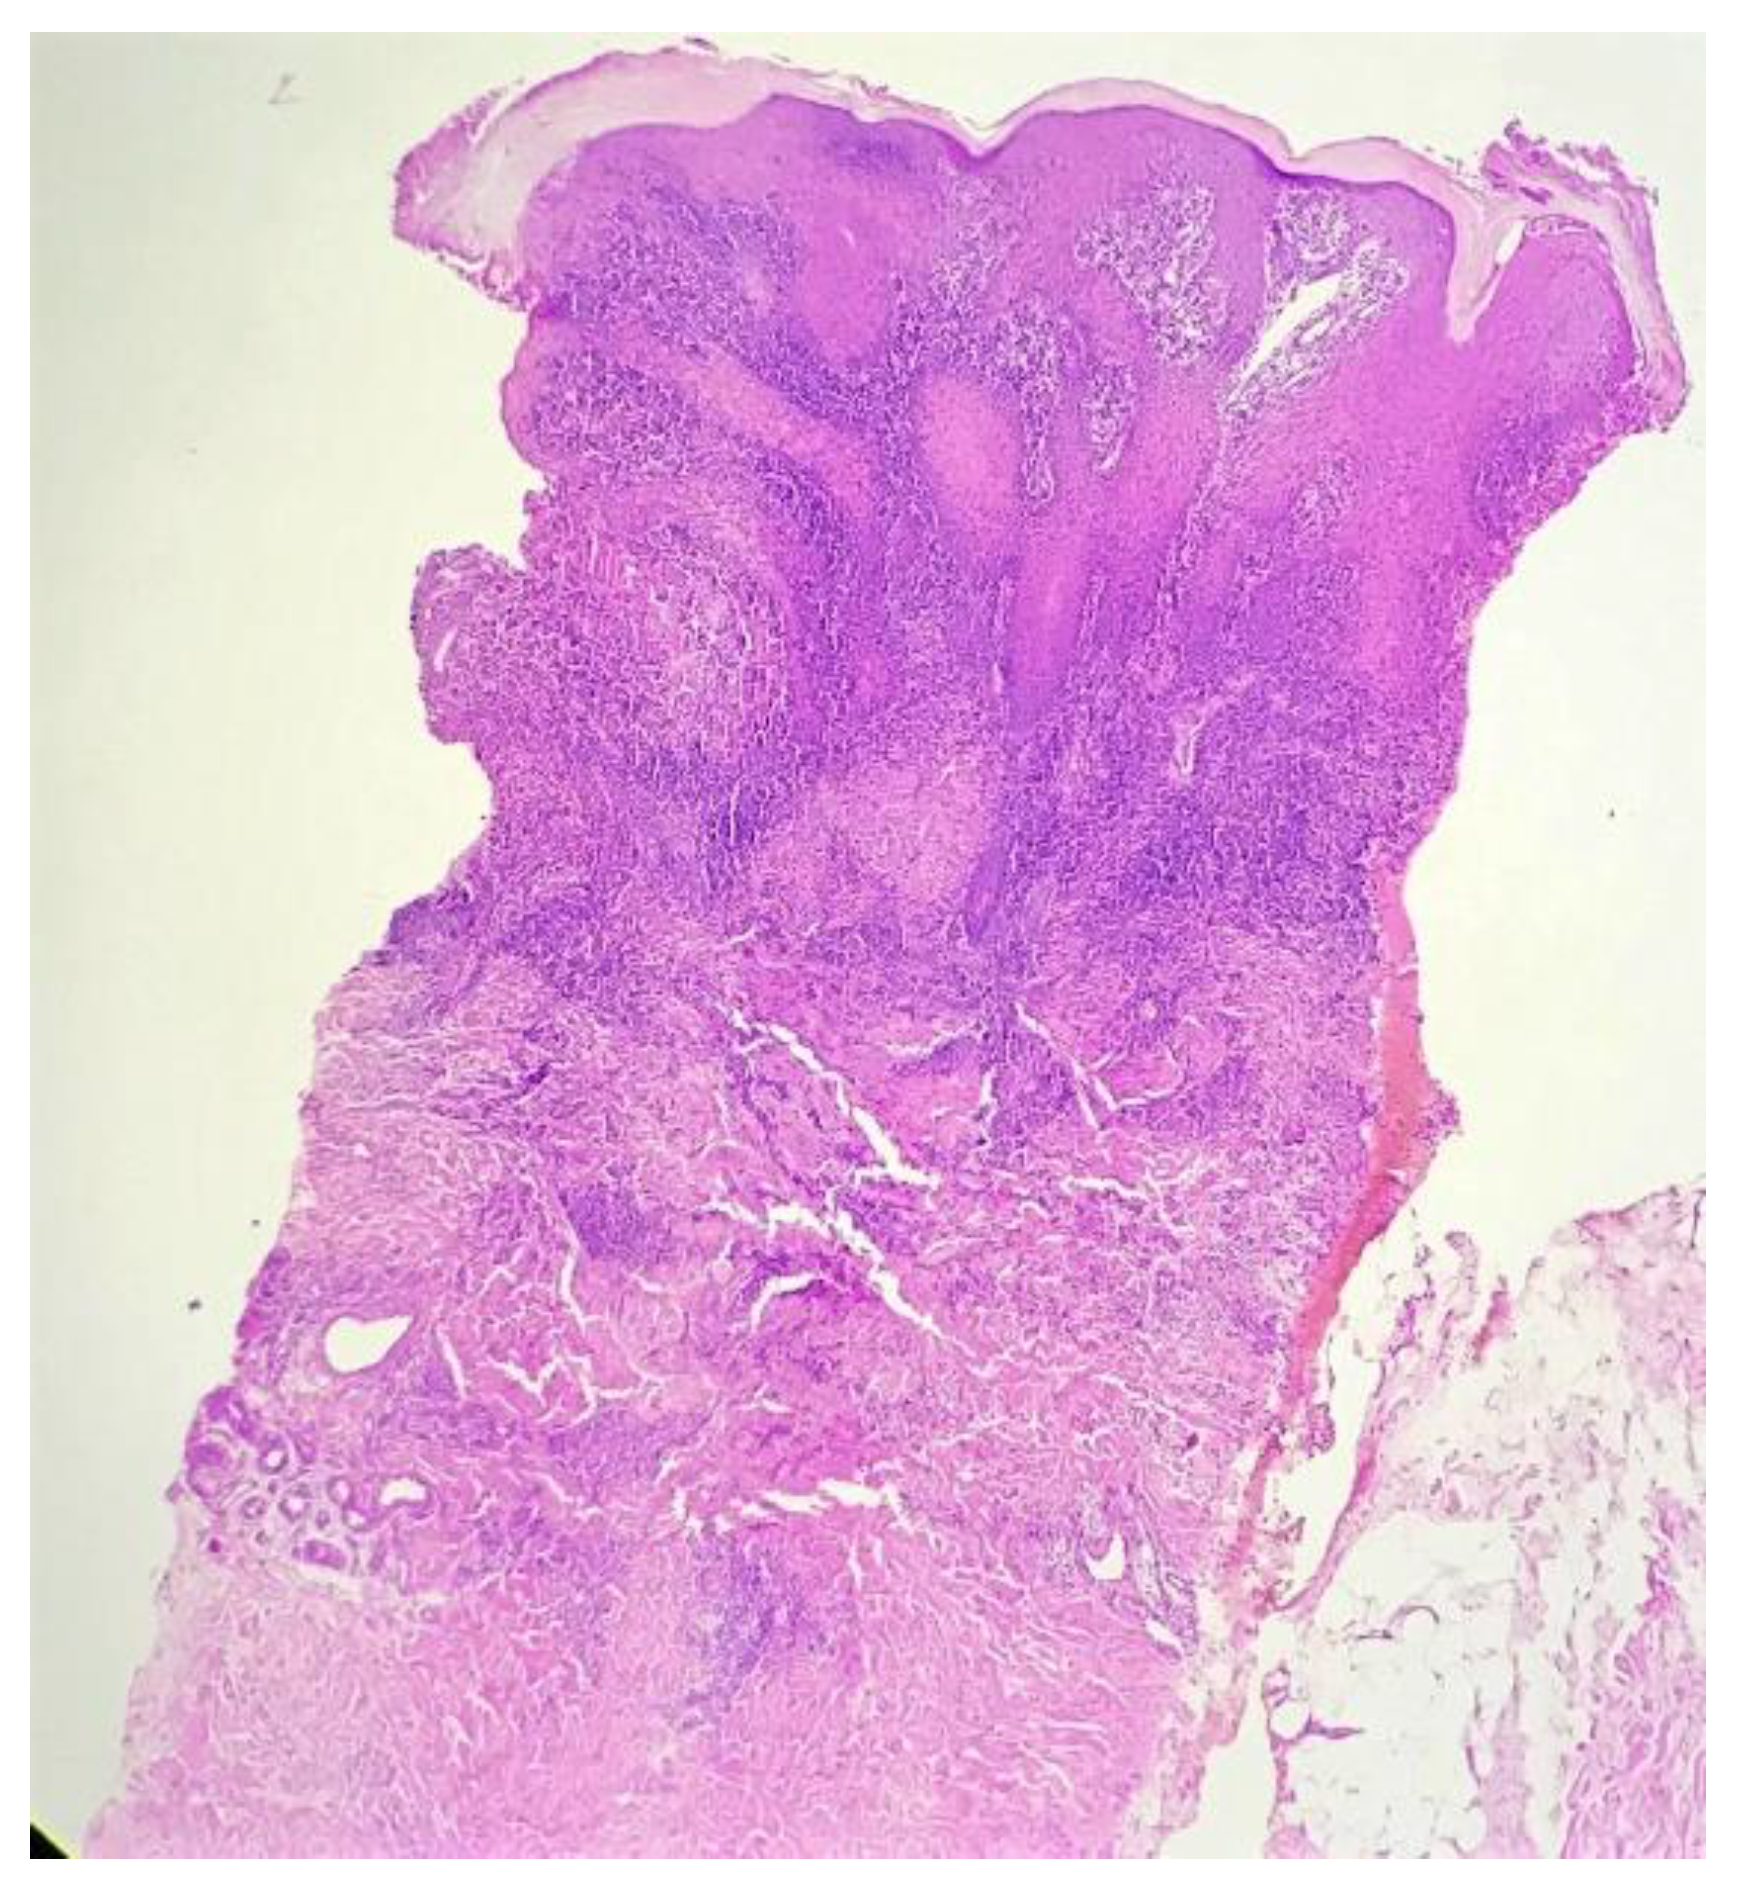

Biopsy showed a dense lichenoid and loose tuberculoid granulomatous infiltrate comprising of epithelioid cells, histiocytes and occasional Langhan’s giant cells, surrounded by lymphocytes and few plasma cells. The granuloma was seen abutting the overlying epidermis, which showed psoriasiform hyperplasia with mild to moderate spongiosis. A compact tuberculoid granuloma was also seen in the deep reticular dermis. Fibroplasia was also seen in the dermis (Figure 2, Figure 3, Figure 4 and Figure 5). The PAS-stained sections were negative for fungal organisms. Zeil–Neelsen stained sections did not reveal any acid-fast bacillus. Based on these features, a diagnosis of lupus vulgaris was favoured and further confirmation by culture study and PCR was advised.

Figure 2. Lichenoid granulomatous dermatitis pattern with psoriasiform epidermal hyperplasia (H&E × 40).